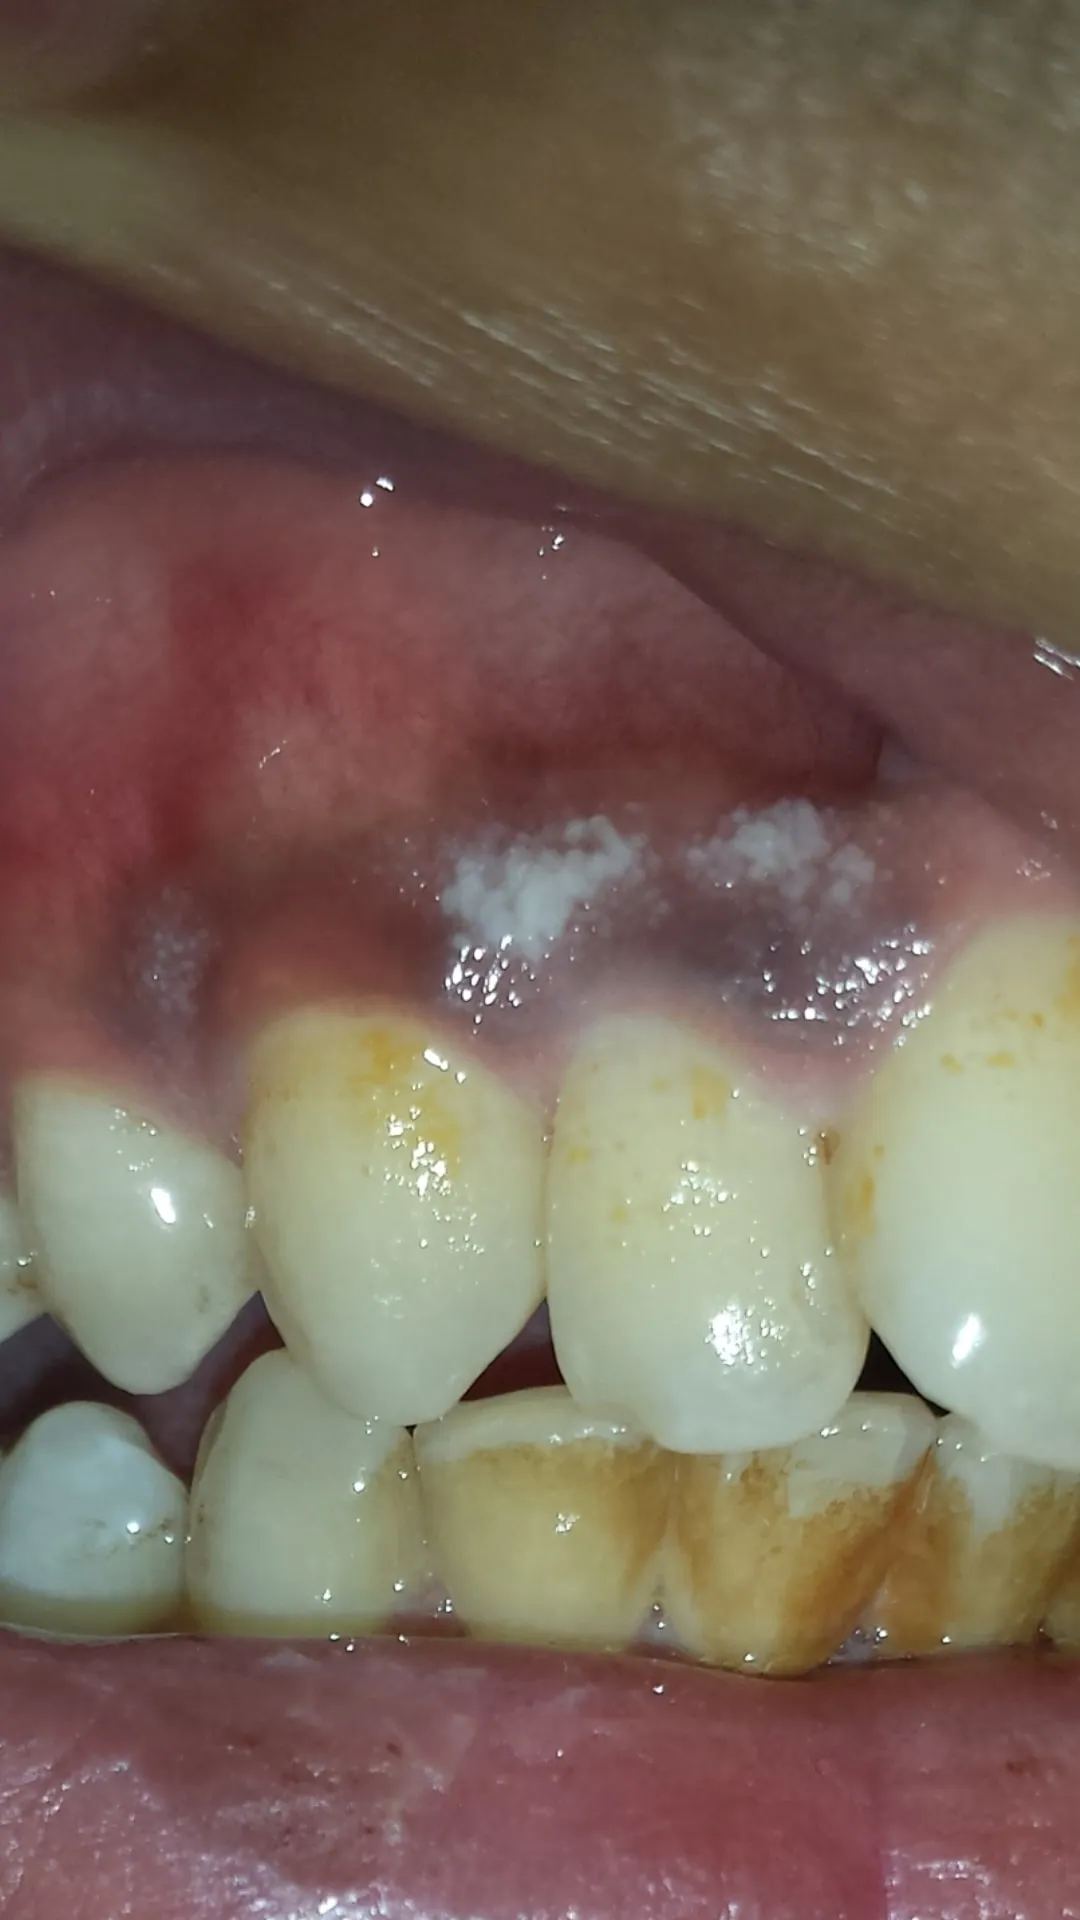

What Causes White Spots After Whitening?

Several factors contribute to the formation of white spots on gums following teeth whitening. These spots primarily result from changes in the gums’ tissues, triggered by the whitening agents. The most common causes include dehydration, chemical irritation from the whitening products, and alterations in the enamel structure. It’s crucial to be aware of these factors to take preventive measures. Whitening agents, often containing hydrogen peroxide or carbamide peroxide, can interact with gum tissues, leading to inflammation and changes in their appearance. Understanding these causes is essential for those considering teeth whitening. Knowing the potential risks and how they manifest helps you make informed choices and discuss strategies for prevention with your dentist, ensuring a safer and more effective teeth-whitening journey.

Chemical Irritation from Whitening Products

Chemical irritation from the whitening agents is another significant cause. The active ingredients in teeth whitening products, such as hydrogen peroxide, can irritate the delicate gum tissues. When these chemicals come into contact with the gums, they can cause inflammation and, in some cases, chemical burns, leading to white spots. The concentration of the whitening agent and the duration of exposure play a role in the severity of this irritation. Using products with lower concentrations or undergoing professional whitening, where gums are carefully protected, can help prevent this issue. Always follow the instructions provided with the whitening product and consider consulting your dentist about the best approach to minimize chemical exposure and protect your gum health during the whitening process.